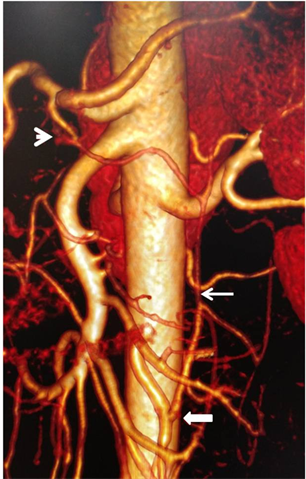

total of 9 patients or 5.6%. Of these, left hepatic artery (Figure 4) and lower right diaphragmatic artery were the most common with three patients each. Then common celiac and mesenteric trunk followed (Figure 5) with 5 patients.

As for quadrifurcation, there were two types. One had a gastro-duodenal artery (Figure 6) and another had a right hepatic artery associated with a left hepatic artery (Figure 7). One patient among the 3 carriers of a collateral corresponding to a left hepatic artery presented two singularities: a trifurcation made

of two right hepatic arteries and the splenic artery (Figure 8), a “pseudo-arc” of Buhler, stretched between the celiac trunk and the inferior mesenteric artery (Figure 9). Table 2 summarizes all the AVs encountered with their frequencies.

Figure 8. Enhanced abdominal CT-scan on 3D reconstruction showing two right hepatic arteries (arrow head and hollow arrow), a left hepatic artery of collateral disposition (thick arrow), a splenic artery (thin arrow) and a gastric artery originating from superior mesenteric artery (hatched arrow).

Figure 9. Enhanced abdominal CT-scan on 3D reconstruction showing a “pseudo-arch” of Buhler indicated by a thin arrow whose proximal end is celiac (arrow head) and the distal end is inferior mesenteric (thick arrow).